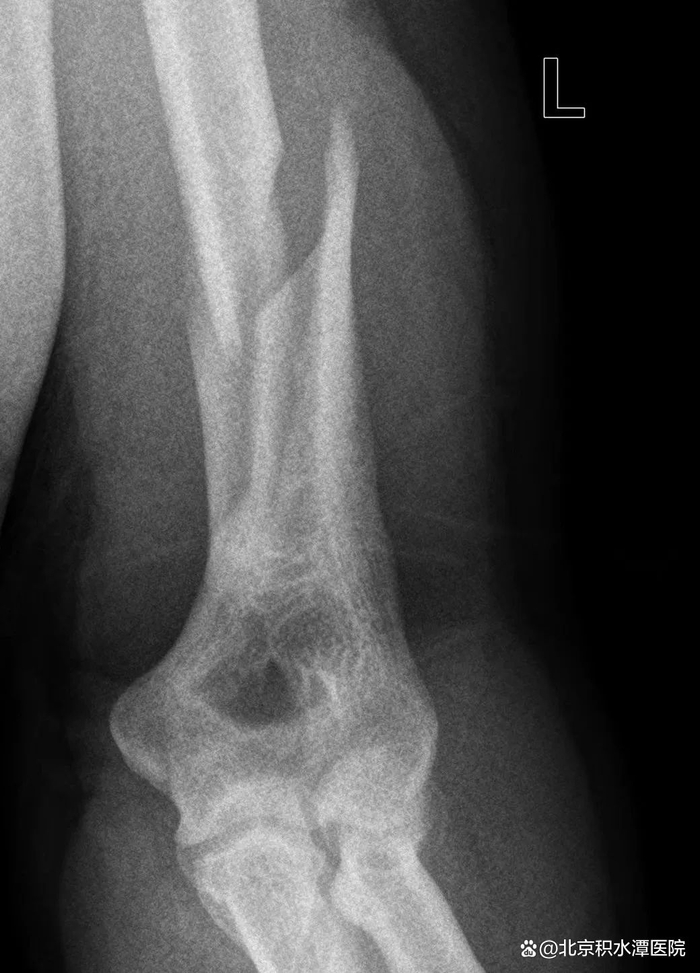

由于存在共同的受伤机制,扳手腕导致的肱骨干骨折表现极为相似。这类骨折几乎都是肱骨远端三分之一螺旋形骨折,半数伴有蝶形骨折片,在AO/OTA分型中分别为12-A1型和12-B1型,可伴有桡神经损伤。

扳手腕导致肱骨干骨折的危险因素包括

反复扳手腕运动史(大于2年)、饮酒和赛前缺乏热身。